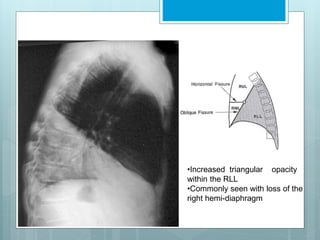

•Increased triangular opacity

within the RLL

•Commonly seen with loss of the

right hemi-diaphragm

RLL Collapse

 Collapse is in post, med & inf

direction.

 Major fissure swings down

&backward.

 Hilum is displaced inferiorly.

 Hemidiaphragm is elevated.

 On PA view a triangular opacity

adjacent to spine with base on

hemidiaphragm.

 On lateral view there is

increased opacity over lower

thoracic vertebrae .